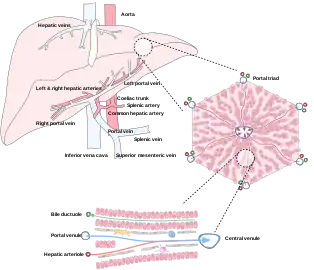

The liver is connected to two large blood vessels: the hepatic artery and the portal vein. The hepatic artery carries oxygen-rich blood from the aorta via the celiac trunk, whereas the portal vein carries blood rich in digested nutrients from the entire gastrointestinal tract and also from the spleen and pancreas.[8] These blood vessels subdivide into small capillaries known as liver sinusoids, which then lead to hepatic lobules.

Microscopic anatomy

Microscopically, each liver lobe is seen to be made up of hepatic lobules. The lobules are roughly hexagonal, and consist of plates of hepatocytes, and sinusoids radiating from a central vein towards an imaginary perimeter of interlobular portal triads.[22] The central vein joins to the hepatic vein to carry blood out from the liver. A distinctive component of a lobule is the portal triad, which can be found running along each of the lobule's corners. The portal triad consists of the hepatic artery, the portal vein, and the common bile duct.[23] The triad may be seen on a liver ultrasound, as a Mickey Mouse sign with the portal vein as the head, and the hepatic artery, and the common bile duct as the ears.[24]

Histology, the study of microscopic anatomy, shows two major types of liver cell: parenchymal cells and nonparenchymal cells. About 70–85% of the liver volume is occupied by parenchymal hepatocytes. Nonparenchymal cells constitute 40% of the total number of liver cells but only 6.5% of its volume.[25] The liver sinusoids are lined with two types of cell, sinusoidal endothelial cells, and phagocytic Kupffer cells.[26] Hepatic stellate cells are nonparenchymal cells found in the perisinusoidal space, between a sinusoid and a hepatocyte.[25] Additionally, intrahepatic lymphocytes are often present in the sinusoidal lumen.[25]

Microscopic anatomy of the liver

Microscopic anatomy of the liver Types of capillaries–sinusoid on right

Blood supply

The liver receives a dual blood supply from the hepatic portal vein and hepatic arteries. The hepatic portal vein delivers around 75% of the liver's blood supply and carries venous blood drained from the spleen, gastrointestinal tract, and its associated organs. The hepatic arteries supply arterial blood to the liver, accounting for the remaining quarter of its blood flow. Oxygen is provided from both sources; about half of the liver's oxygen demand is met by the hepatic portal vein, and half is met by the hepatic arteries.[40] The hepatic artery also has both alpha- and beta-adrenergic receptors; therefore, flow through the artery is controlled, in part, by the splanchnic nerves of the autonomic nervous system.

Blood flows through the liver sinusoids and empties into the central vein of each lobule. The central veins coalesce into hepatic veins, which leave the liver and drain into the inferior vena cava.[41]

The liver and its veins Diagram of liver, lobule, and portal tract and their inter-relations

Diagram of liver, lobule, and portal tract and their inter-relations

Biliary flow

The biliary tract is derived from the branches of the bile ducts. The biliary tract, also known as the biliary tree, is the path by which bile is secreted by the liver then transported to the first part of the small intestine, the duodenum. The bile produced in the liver is collected in bile canaliculi, small grooves between the faces of adjacent hepatocytes. The canaliculi radiate to the edge of the liver lobule, where they merge to form bile ducts. Within the liver, these ducts are termed intrahepatic bile ducts, and once they exit the liver, they are considered extrahepatic. The intrahepatic ducts eventually drain into the right and left hepatic ducts, which exit the liver at the transverse fissure, and merge to form the common hepatic duct. The cystic duct from the gallbladder joins with the common hepatic duct to form the common bile duct.[41] The biliary system and connective tissue is supplied by the hepatic artery alone.